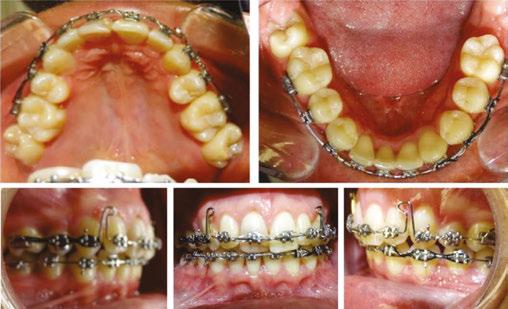

January 21, 2021 and had all extractions completed on February 10, 2021. Within 5 days of the extractions taking place, power chains were placed to close extraction spaces and preserve remaining alveolar bone and minimize adaptive bone resorption of the extraction sites. (Figures 7A, 7C, and 7E).

At this stage in treatment, our main goal was to level and align, close extraction spaces to relieve crowding, and monitor any signs of ankylosed teeth. Rotations on the mandibular teeth were corrected in a .016 NiTi wire (Figures 7C and 7E versus Figures 8C and 8E). Efforts were made to minimize roundtripping of incisors via bypassing upper left lateral incisor.

Once appropriate anchorage was burned, and the spaces between the maxillary canines and first molars were closed, a closing looped arch wire was bent using a .018 x .025 stainless steel wire (.018 anterior slot size, Roth Rx) and placed on October 13, 2022. This wire aided in correcting torque, retracting the maxillary anterior teeth, bite opening, and closing remaining spaces between the maxillary canines and lateral incisors (Figures 9C and 9E). At the same time, power chains were used to consolidate remaining spacing in the lower arch (Figures 9B and 9E).

Minor adjustments in torque were then resolved with .016 x .022 NiTi wires placed on June 22, 2022. By October 19, 2022, the patient’s spaces were consolidated, and all teeth were properly leveled and aligned. The finishing stage of treatment (Figure 10) involved minor detailing and Class II elastic wear. The tissue is healthy, spaces are consolidated, the patient is happy with the current esthetic result.

Figure 7: Progress intraoral photos taken on February 10, 2021 Figure 8: Progress intraoral photos taken on April 7, 2021 Figure 9: Progress intraoral photos taken March 3, 2022 Figure 10: Progress extraoral (Figures 9A–9C) and intraoral (Figures 9D–9H) photos taken January 18, 2023 A. A. A. A. D. F. G. H. B. E. C. C. C. C. D. D. D. E. E. E. B. B. B.